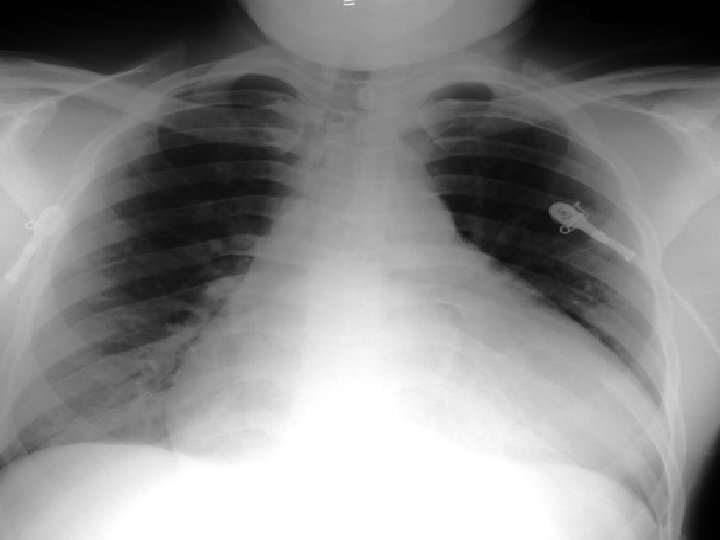

Critérios diagnósticos Framingham Definida: 2 sinais maiores 1 sinal maior e 2 menores Sinais Maiores – DPN ou ortopnéia – Ingurgitamento jugular – Estertores finos nas bases – Cardiomegalia – EAP – B 3 – RHJ – Perda de ≥ 4, 5 Kg em 5 dias, em resposta ao tto Sinais Menores – – – – Dispnéia aos esforços Tosse noturna Edema de MMII Hepatomegalia Derrame pleural FC>120 bpm Diminuição da capacidade vital (<1/3 da registrada)

Exames de Avaliação inicial -ICC • Avaliação Clínica – – • • Sistólica x diastólica Etiologia Estadio e CF Prognóstico ECG RX Tórax Ecocardiograma Lab – – Hemograma Função tireoidiana Bioquímica BNP